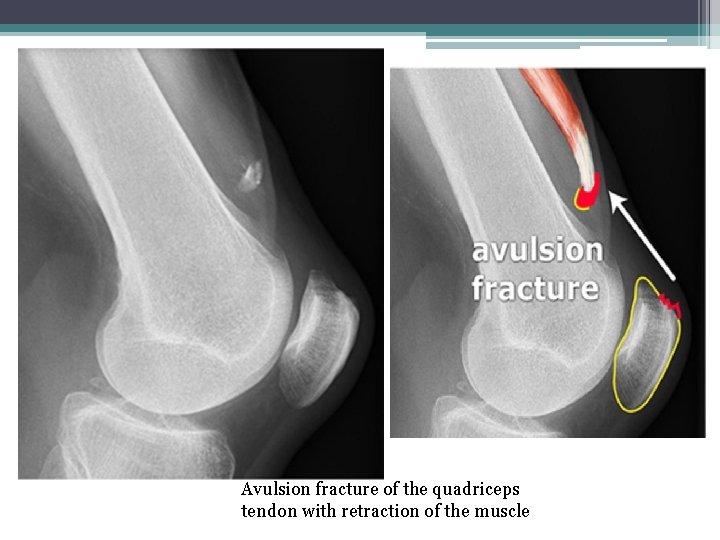

• 3 -Avulsion Fracture: a muscle or ligament pulls on the bone, fracturing it (a fragment of bone is detached from the site of a ligament or tendon insertion).

Avulsion fracture of the quadriceps tendon with retraction of the muscle